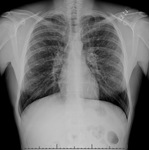

Chest x-ray in a patient with bronchogenic carcinoma showing a left-sided pleural effusion

From: R. Thakkar, Student BMJ. 2001;9:458